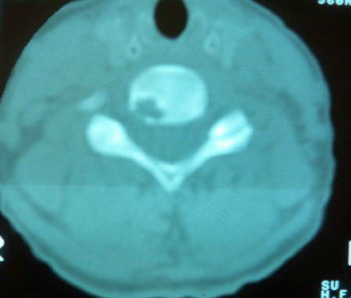

女。70 主因 头晕

颈椎周围软组织无明显变化,颈椎右后缘见低密度影,外周见硬化带,考虑许莫氏结节。

颈椎右后缘见低密度影,无明显分隔,外周见硬化带,周围软组织未见异常,考虑许莫氏结节。